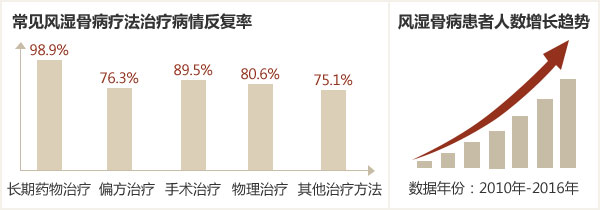

风湿病严峻形式: 常见疗法种种伤害

卫生部数据显示:我国患类风湿、痛风、强直等风湿病病人占全国总人口的18%,50岁以上老年人发病率60%,其中53%严重破坏关节功能。这种情况正是由于不少病人未能及时治疗或采取错误疗法治疗造成的,而中医微创可视针刀镜技术则突破以往局限,从关节病灶出发,诊治同步,快速清除病变组织,恢复关节功能,已成为我国风湿病临床治疗的一次重大革新。